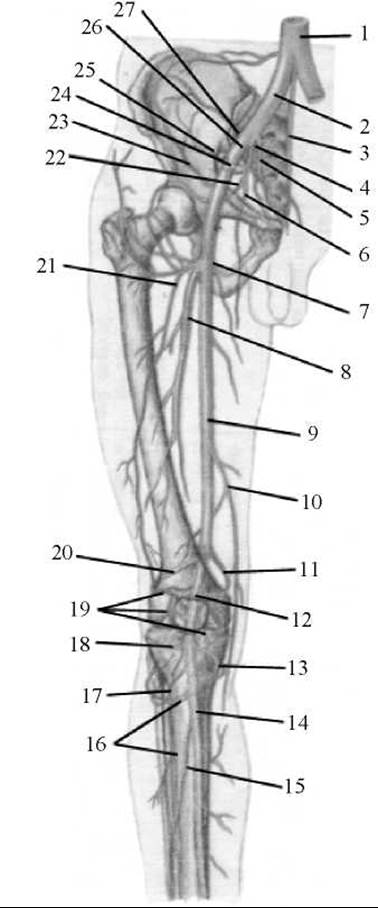

Мал. 209. Артерії таза, стегна та гомілки правої нижньої кінцівки (півсхематично)

1 — Черевна частина аорти; 2 — спільна клубова артерія; 3 — серединна крижова артерія; 4 — внутрішня клубова артерія; 5 — бічна крижова артерія; 6 — затульна артерія; 7 — присередня артерія, огинаюча стегнову кістку; 8 — глибока артерія стегна; 9 — стегнова артерія; 10 — низхідна колінна артерія; 11 — присередня верхня колінна артерія; 12 — підколінна артерія; 13 — присередня нижня колінна артерія; 14 — задня великогомілкова артерія; 15 — малогомілкова артерія; 16 — передня великогомілкова артерія; 17 — передня поворотна великогомілкова артерія; 18 — бічна нижня колінна артерія; 19 — колінна суглобова (артеріальна) сітка; 20 — бічна верхня колінна артерія; 21 — бічна артерія, огинаюча стегнову кістку; 22 — нижня сіднична артерія; 23 — глибока огинаюча клубова артерія; 24 — нижня надчеревна артерія; 25 — верхня сіднична артерія; 26 — зовнішня клубова артерія; 27 — клубово-поперекова артерія